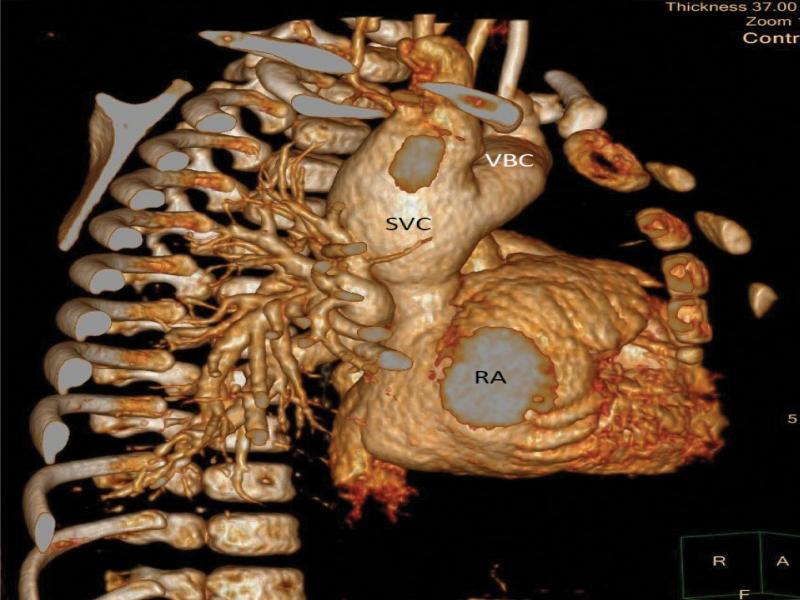

The heart seen from the right side, 3D angio-CT reconstruction. From this perspective, the unusual dilatation of the distal SVC as well as the left brachiocephalic vein (VBC) with relatively narrow proximal part of SVC is more apparent